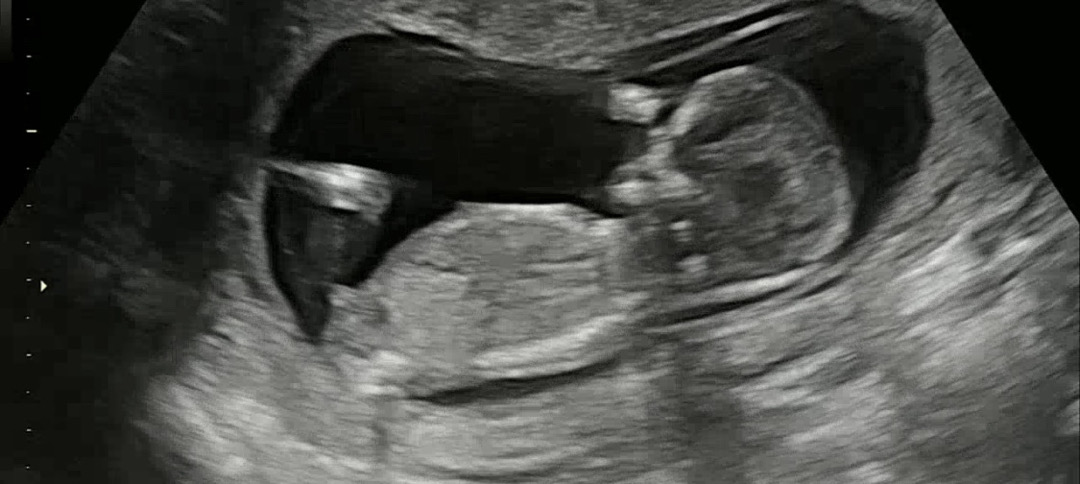

12주4일 각도법 봐주세요~!

제 눈에는 아들 같은데 어때보이세요??!!